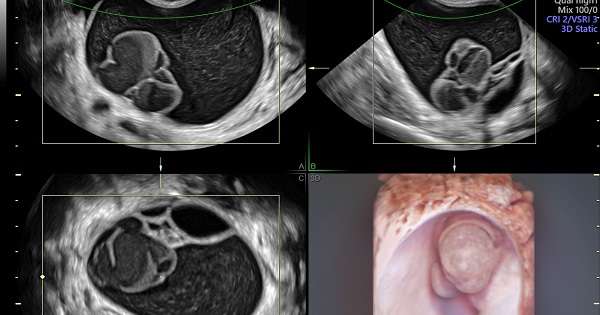

Hút cả lít dịch cứu người phụ nữ đi tiểu 15 lần mỗi đêm(NLĐO) - Người phụ nữ có khối u to như thai 28 tuần đè bàng quang gây tiểu lắt nhắt kinh niên và được bác sĩ hút ra hơn 2 lít dịch.